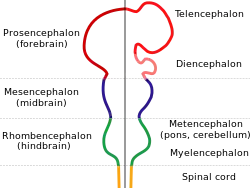

| Embryonic brain | |

It is suggested that the underdevelopment or lack of white matter in the developing fetus could be a cause of colpocephaly. The partial or complete absence of white matter, also known as agenesis of the corpus callosum results in anatomic malformations that can lead to colpocephaly. This starts to occur around the middle of the second month to the fifth month of pregnancy. The lateral ventricles are formed as large cavities of the telencephalic vesicle. The size of the ventricles are decreased in normal development after the formation of the Foramen of Magendie, which decompresses the ventricular cavities. Myelination of the ventricular walls and association fibers of the corpus callosum and the calcarine fissure helps shape the occipital horns. In cases where this developmental process is interrupted, occipital horns are disproportionately enlarged.[4]